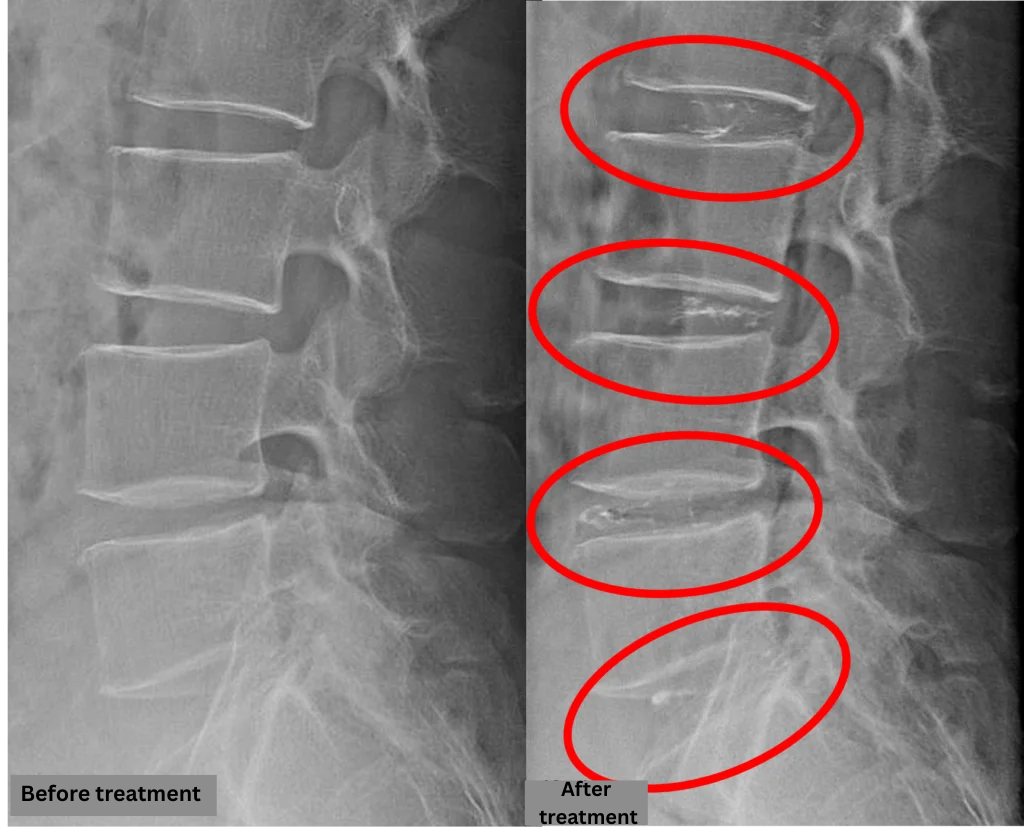

- L2/3, L3/4, L4/5: Disc degeneration and disc bulging

- L5/S1: Disc degeneration, disc bulging, annular tear

The above findings were also observed on the imaging.

The imaging confirmed disc degeneration and protrusion across multiple levels. It is highly likely that spinal canal compression caused by the disc findings at L2/3, 3/4, 4/5, and L5/S is the primary cause of the symptoms.

After consulting with the patient, the Cellgel Method was performed on L2/3, 3/4, 4/5 and 5/s.